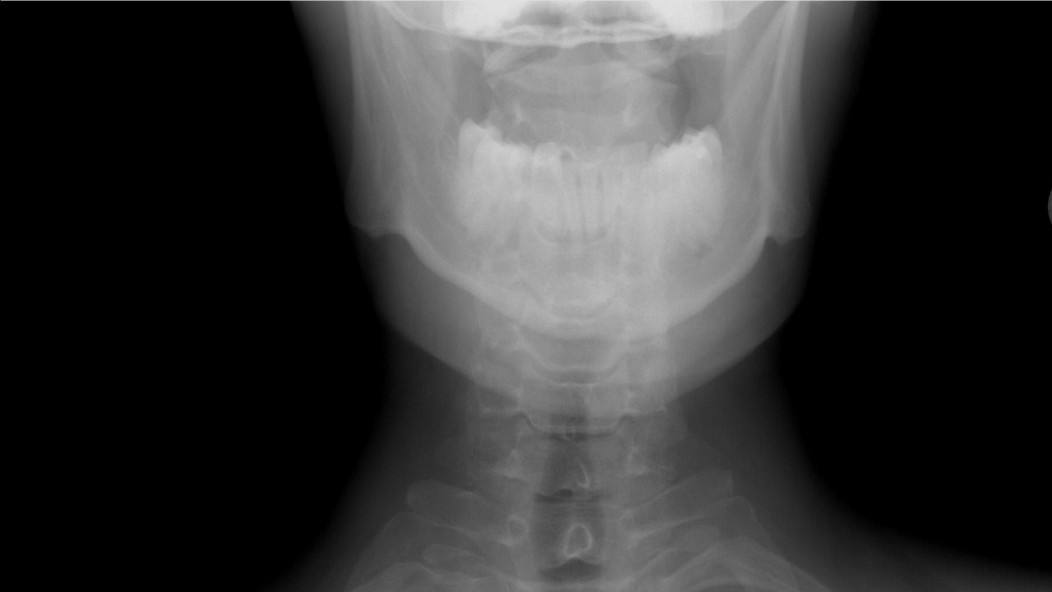

В Челябинске школьница сломала три позвонка на уроке физкультуры В одной из школ Челябинска произошло ЧП на уроке физкультуры ученица 6 класса выполняя кувырки получила серьезную травму На уроке физкультуры на котором учитель демонстрировал технику выполнения кувырков девочка как и многие ее одноклассники демонстрировала свои навыки Однако после второй попытки выполнения упражнения она почувствовала резкую боль в области шеи Сразу после инцидента школьница была отправлена в медпункт где ей оказали первую помощь Однако состояние ребенка требовало более серьезного вмешательства и вскоре пострадавшую доставили в больницу Врачи провели обследование и выявили компрессионные переломы трех позвонков Это означает что 6 класснице предстоит долгий путь к восстановлению около полугода она будет вынуждена носить специальный корсет Мать пострадавшей девочки выразила недовольство действиям сотрудников школы Женщина утверждает что скорую помощь педагоги вызывать не спешили что могло усугубить состояние ребенка В учебном заведении где произошел инцидент началась внутренняя проверка

В Челябинске возбудили уголовное дело из за перелома позвоночника у школьницы на уроке Об этом сегодня сообщили в региональном управлении Следственного комитета Сотрудники ведомства разбираются в деталях случившегося Истребованы медицинские документы назначена судебно медицинская экспертиза проведен осмотр места происшествия осуществляются допросы очевидцев и сотрудников школы пояснили в ведомстве В СК также уточнили что уголовное дело возбуждено по статье Халатность Инцидент в одной из школ Челябинска произошел во время урока физкультуры По словам родителей пострадавшей на занятии выполняли кувырки позже у девочки диагностировали компрессионные переломы трех позвонков Фото ГТРК Южный Урал Подписывайтесь на Вести Южный Урал в MAХ

В Челябинске шестиклассница докувыркалась сломала позвоночник на уроке физкультуры 20 ноября образовательном центре 5 шестиклассница получила тяжелую травму во время урока физкультуры Выполняя кувырок девочка почувствовала резкую боль в шее Как пишет 74 RU ученица сделала упражнение неправильно и педагог попросила её повторить после чего и случилась травма После жалоб ученицы учитель просто посадила её на лавочку Подруги отвели девочку в медпункт но школьная медсестра долго не хотела вызывать скорую пока мать пострадавшей не настояла на этом В больнице врачи диагностировали компрессионные переломы трех позвонков Теперь девочке предстоит полгода провести лежа в специальном корсете Школа начала внутреннюю проверку и пообещала оказать семье всестороннюю помощь 74 RU Уралити